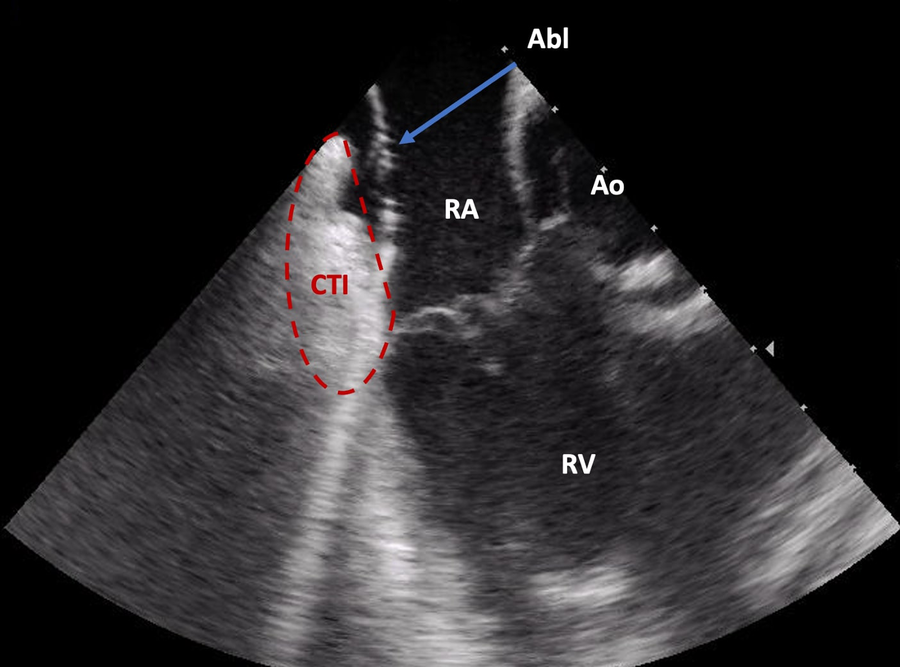

Figure 2

Direct visualization of the ablation catheter on the cavotricuspid isthmus by intracardiac echocardiography (ICE). Abl, ablation catheter; Ao, aortic root; CTI, cavotricuspid isthmus; RA, right atrium; RV, right ventricle.